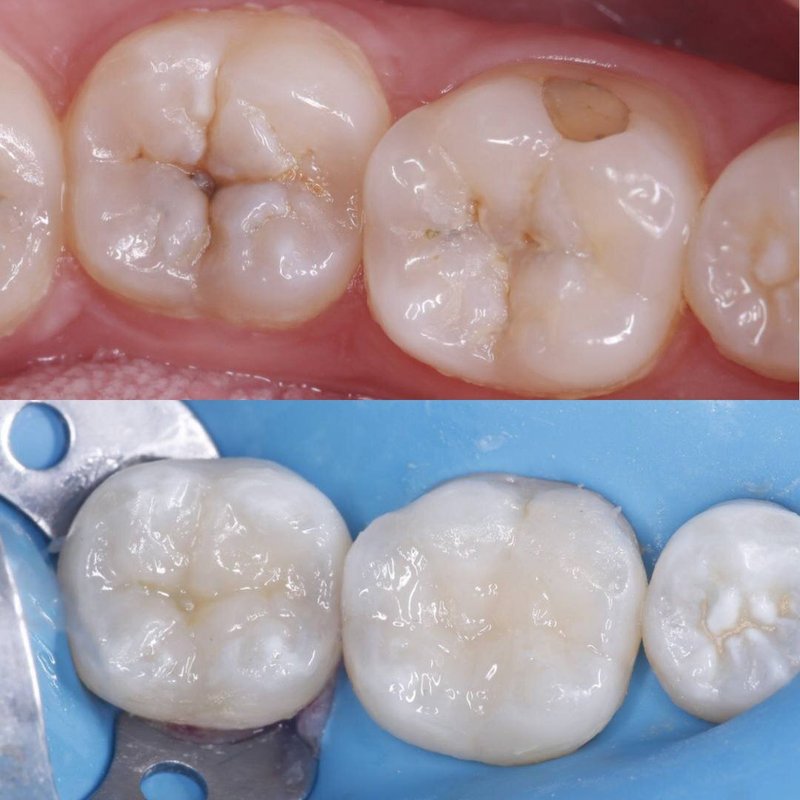

Фотогалерея